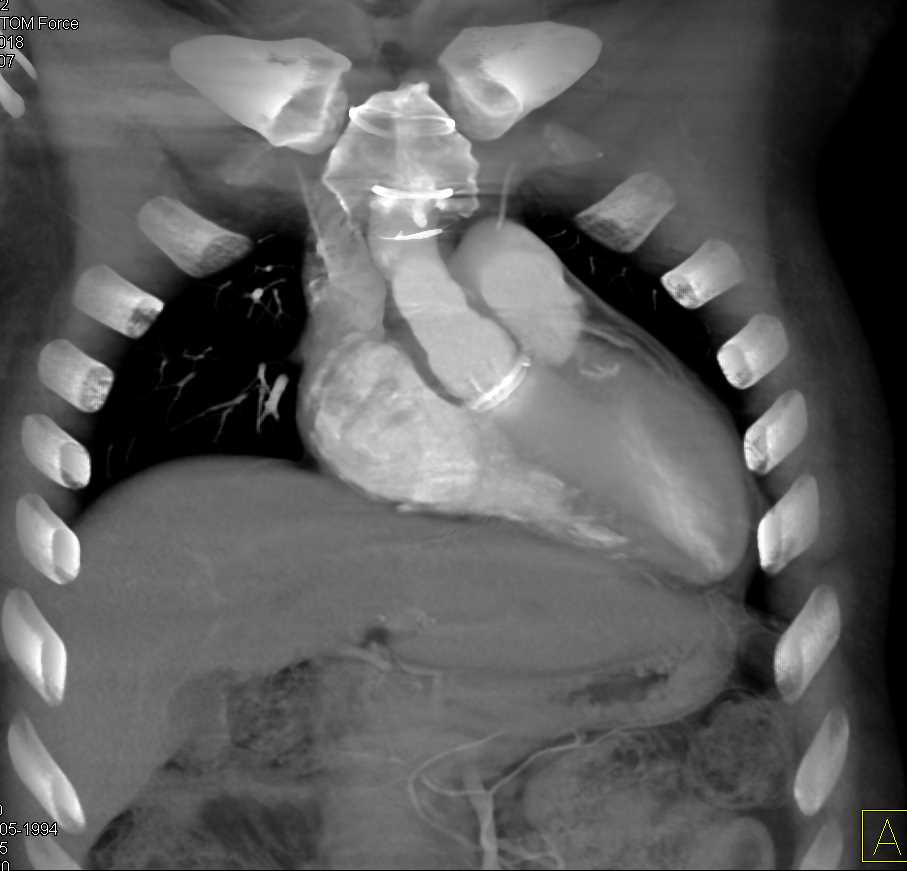

Aortic Valve Repair